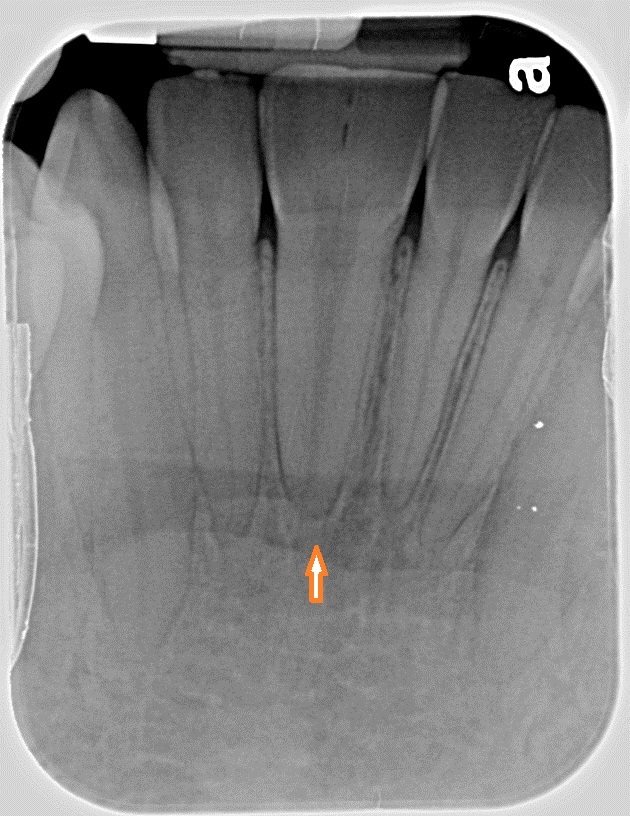

What’s happening with the tooth in the marked area?

Dens invaginatus